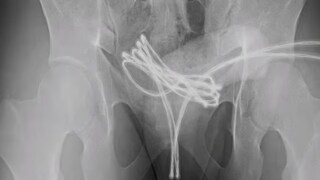

जेव्हा डॉक्टरांनी तपासणी केली, तेव्हा आढळले की केबल मूत्राशयात पोहोचली होती आणि तिथेच अडकली होती. 'क्युरियस' जर्नलमध्ये प्रकाशित झालेल्या अहवालानुसार, डॉक्टरांनी आधी हाताने केबल काढण्याचा प्रयत्न केला, पण ते यशस्वी झाले नाहीत. शेवटी, मुलाला बेशुद्ध करून विशेष उपकरणांच्या मदतीने केबल काढण्यात आली. डॉक्टरांनी हळू हळू केबल बाहेर ओढली, नंतर ती कात्रीने कापली आणि दोन्ही भाग सहज बाहेर काढले.